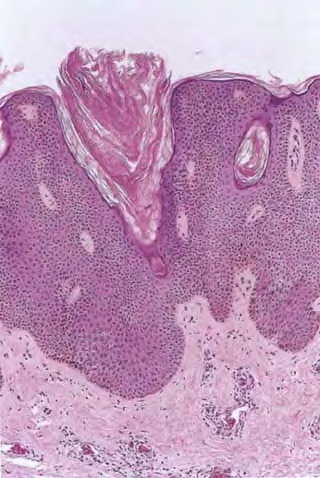

Seborrheic keratoses = التقران الدهني